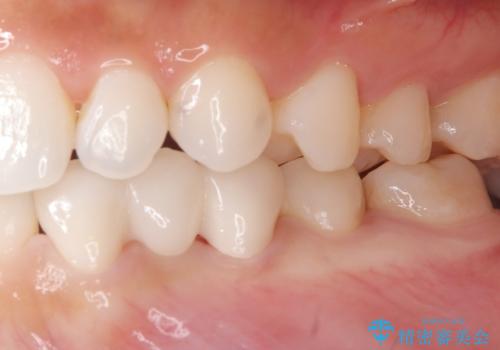

欠損歯をブリッジにて補綴

矯正治療にてスペースを一箇所に集めてからオールセラミックブリッジにて補綴治療を行いました。

- 36万円費用は治療当時の料金となります

今回は、患者様の希望もありインプラントではなくブリッジにて修復しています。